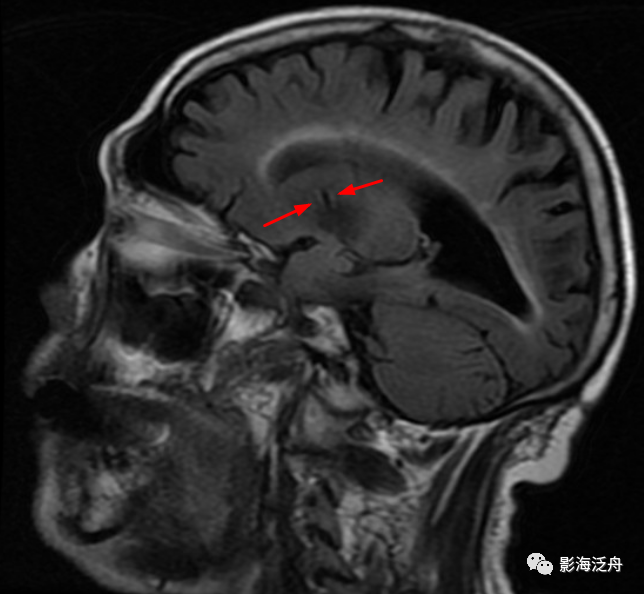

III型-中脑型:左侧大脑脚可见细条状T2WI高信号影(红箭),Flair序列上未见异常信号(黄圈为中脑左侧部),随访病灶大小及信号均无明显变化。III型VR腔隙扩大是最少见的,多数审核老师喜欢不分青红皂白直接诊断为腔梗灶,毕竟是脑干区域,报的过一点也无妨。